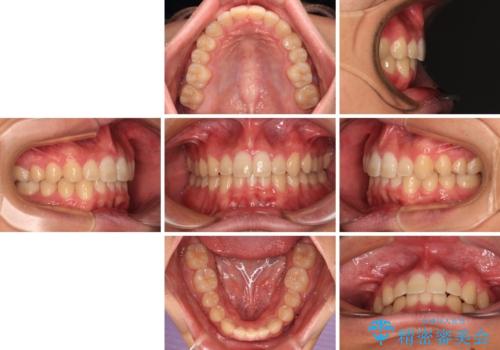

- 上下前歯のデコボコと深い咬み合わせを気にして来院された患者様です。

下顎前歯が一本欠損しており、下顎の歯列が小さいため、ディープバイトになりやすい状態でした。

傾斜しいている大臼歯を立ち上げながら、下顎歯列を上顎に対して前方位となるように工夫し、デコボコを解消した上でディープバイトも改善することができました。